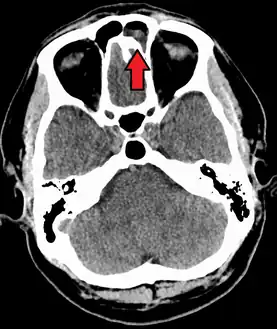

| A CT scan showing sinusitis of the ethmoid sinus | |

CT of chronic sinusitis

CT scan of chronic sinusitis, showing a filled right maxillary sinus with sclerotic thickened bone.